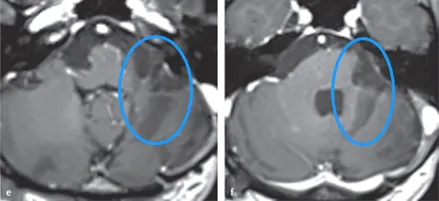

术后活检结果:H先生手术后经病理检查为胶质母细胞瘤,IDH1和BRAFN阴性;p53蛋白的局部阳性率高达50%,而O6-甲基鸟嘌呤DNA甲基转移酶(MGMT)启动子高度甲基化。H先生术后按Stupp方案进行放化疗。术后随访MRI显示剩余肿瘤逐渐消退,患者临床表现持续良好。

术后4年,患者可以完全独立生活,延髓(图e)和脑桥(图f)轴位t1加权磁共振增强扫描未见肿瘤残留或复发。

H男士术后MR影像